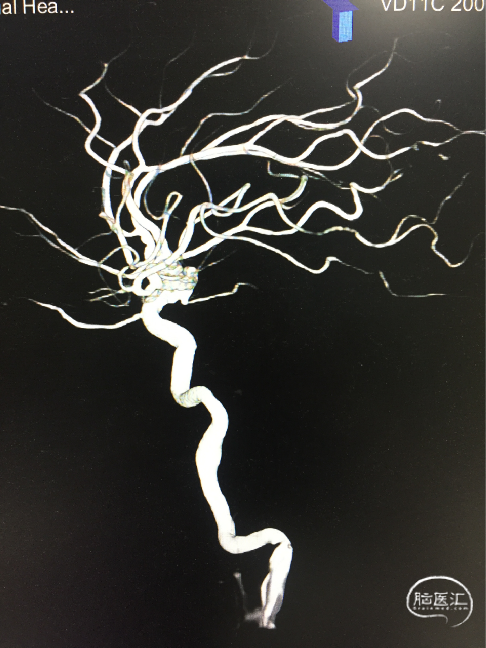

术前DSA 3D:左颈内动脉正侧位及工作位,前交通动脉瘤,约4×8mm,颈宽约6.5mm,形态宽颈、分叶。前交通动脉及大脑前动脉A1、A2直径约2mm。